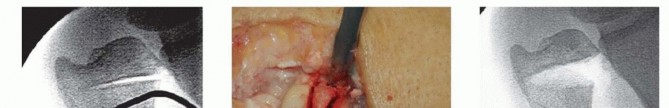

TECH FIG 7 • A. Fluoroscopic image of distal osteotomy, proximal to the sigmoid notch. B. Completion of radial wedge osteotomy. Bone wedge is removed using an osteotome. C. Fluoroscopic image of completed radial wedge osteotomy. D. Placement of headless compression screw over Kirschner wire. E. Radiograph after screw placement showing osteotomy compression. (From Slade JF III, Gillon TJ. Osteochondral shortening osteotomy for the treatment of ulnar impaction syndrome: a new technique. Tech Hand Up Extrem Surg 2007;11:74-82.)Based on preoperative determinations, resect a 3- to 5-mm wafer of bone using a microsagittal saw at the level of the proximal margin of the DRUJ.Leave the distal ulnar articular surface and the TFCC foveal attachments intact (TECH FIG 7A-C).Reduce and compress the osteotomy with a hemostat and a Kirschner wire placed for temporary stabilization.Intraoperative fluoroscopy is used to confirm the adequacy of resection and osteotomy reduction. More bone can be removed if necessary, up to 5 mm total.Excessive bony resection could lead to DRUJ instability or impingement.Thread a cannulated headless compression screw over the previously inserted Kirschner wire while manual compression is maintained (TECH FIG 7D,E).Remove the Kirschner wire and irrigate the wounds.Repair the dorsal capsule with interrupted nonabsorbable sutures.Transpose the extensor digiti quinti tendon out of the fifth compartment as the capsule is repaired.Close the skin incision with a nonabsorbable monofilament suture, and inject all incisions, as well as the wrist, with a local anesthetic.Place the wrist in a bulky dressing with a volar splint.P.1054